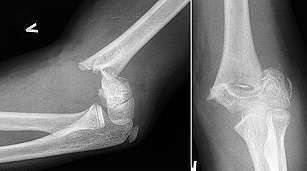

Verletzungen geben Auskunft über die Bewegungsrichtungen, die Konstellation der Kollisionsgegner zueinander und über die Sitzpositionen im Fahrzeug während des Zusammenstoßes. Außerdem dienen sie zur Identifizierung von beteiligten Personen, insbesondere des Fahrers eines Kfz.